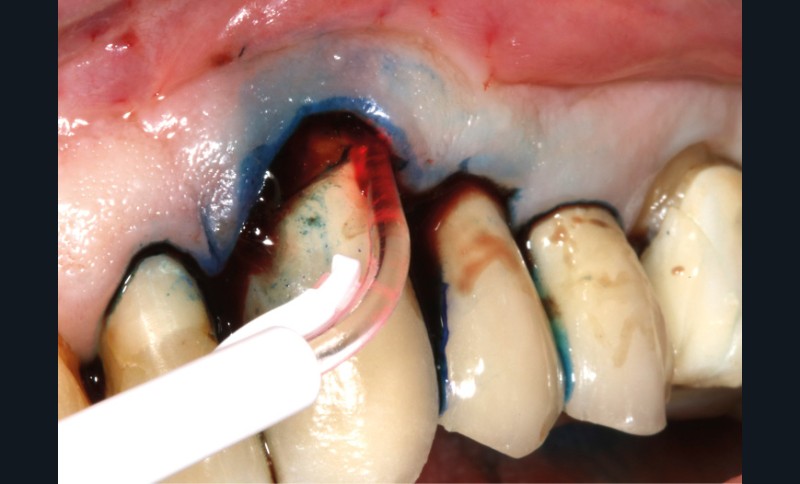

– thérapie photodynamique (bactéricide avec colorant photosensible) pour les lasers de faible énergie (600 à 800 nm),

C’est un laser idéal pour le traitement chirurgical des péri-implantites. Il permet l’élimination du tissu de granulation à la surface de l’implant et de l’os ainsi qu’une décontamination mécanique par effet photoablatif.– Le laser Diode, utilisé pour la décontamination…